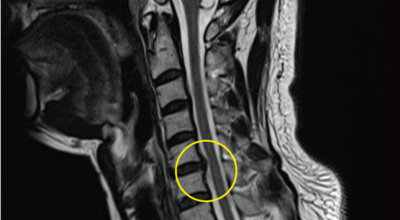

목디스크 증상이 나타날때 빨리 발견하여 비수술 치료를 받고 꾸준히 관리하는 것이 베스트이죠. 목디스크 환자 중 수술을 진행하는 환자는 2% 미만으로 현저히 적다고 해요. 수술을 진행하는 경우는 감각이 느껴지지 않는 마미증후군이나, 한쪽 다리가 눈에 띌 정도로 야윈 경우에만 진행하므로 올바른 자세 교정만으로도 충분히 호전될 수 있는 질병이죠. 목에 연관된 검사는 MRI나 CT를 이용해요. 그러나 전자의 경우 비용이 굉장히 비싸기 때문에 디스크 증세가 확실하다고 생각될 경우에만 선택적으로 하고 의무적으로 하는 건 아니니까 비용에 대해선 부담을 가지지 마시길 바래요.